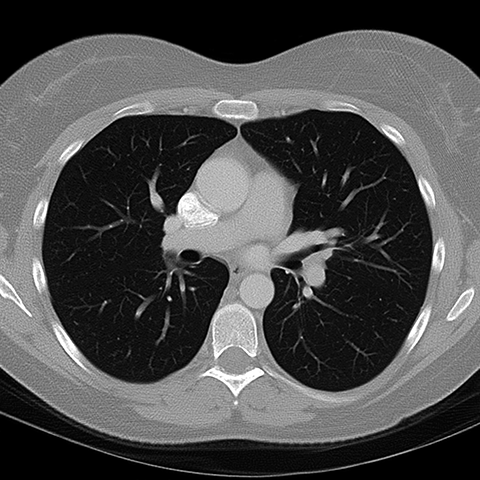

正常增强CT(骨)Normal Contrast-Enhanced CT (Bone Window) [3 of 8]